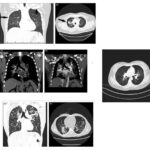

La exploración por tomografía computarizada (TC), que se utilizó por primera vez diez años después de que se describiera el sistema de estadificación Scadding, ha reemplazado desde entonces a la CXR convencional y ha demostrado ser mucho más sensible que la radiografía de tórax para representar anomalías del parénquima pulmonar en pacientes con sarcoidosis.

Aunque las TC son ampliamente utilizadas en pacientes con sarcoidosis, su papel en el seguimiento, el pronóstico y la orientación terapéutica aún no está bien establecido. Se recomienda considerar la TC cuando existan hallazgos clínicos o radiográficos atípicos, sospecha de complicaciones o condiciones superpuestas, sospecha clínica de sarcoidosis con radiografía de tórax normal, o en pacientes candidatos a trasplante pulmonar. La TCAR es preferible debido a su mayor capacidad para detectar anomalías sutiles y distinguir entre fibrosis e inflamación en diferentes estadios de la enfermedad.

Hallazgos en la TCAR en la sarcoidosis

La sarcoidosis pulmonar se caracteriza por varios hallazgos en la tomografía computarizada de alta resolución (TCAR). Estos incluyen linfadenopatía hiliar y paratraqueal bilateral bien definida, opacidades nodulares y micronodulares con distribución perilinfática. Los nódulos son redondeados y suelen tener un tamaño de 2 a 4 mm. También se observa el agrandamiento y calcificación de los ganglios linfáticos hiliares bilaterales. Las calcificaciones pueden presentar diferentes aspectos, como amorfo, puntiforme (parecido a una palomita de maíz) o similar a una cáscara de huevo. La distribución perilinfática de las lesiones micronodulares es el patrón parenquimatoso más frecuente. Con el tiempo, estas lesiones pueden fusionarse y formar macronódulos y conglomerados similares a masas, con la presencia de pequeños nódulos satélites alrededor de las masas conglomeradas, lo que se conoce como “signo de galaxia”.

En la TCAR se pueden encontrar otros hallazgos menos frecuentes, como cambios fibróticos con opacidades lineales y bronquiectasias por tracción, opacidades parcheadas en vidrio esmerilado, consolidación parcheada del espacio aéreo (alveolitis sarcoide o sarcoidosis alveolar), opacidades reticulares lineales aisladas, halo inverso o signo del atolón. La sarcoidosis pulmonar también muestra un patrón de atenuación en mosaico debido a la afectación granulomatosa o fibrosis de las vías respiratorias pequeñas, lo cual puede estar asociado con obstrucción en las pruebas de función pulmonar. El atrapamiento de aire es común pero no específico de la sarcoidosis y puede estar presente en cualquier etapa radiográfica de la enfermedad. Se detectan anomalías traqueobronquiales en la TC, con engrosamiento y estenosis de la pared bronquial, que se correlacionan con los hallazgos broncoscópicos.

La estenosis bronquial puede ser causada por acumulación de granulomas endobronquiales, compresión extrínseca de las vías respiratorias debido a ganglios linfáticos agrandados en el mediastino, o distorsión de los bronquios debido a enfermedad parenquimatosa fibrótica en etapa terminal. El bronquio del lóbulo medio derecho es el más afectado en la sarcoidosis. En casos avanzados y de alto riesgo, la TCAR puede mostrar quistes fibróticos, ampollas y enfisema paracicatricial, que indican una etapa avanzada de la sarcoidosis. Estas lesiones tienden a afectar las zonas pulmonares superiores y medias, siguiendo las vías respiratorias más grandes en una distribución perihiliar. Los cambios quísticos subpleurales en panal se encuentran principalmente en las zonas pulmonares superiores y medias, mientras que las bases pulmonares se ven menos afectadas. Se debe considerar la fibrosis pulmonar idiopática en el diagnóstico diferencial cuando las bases pulmonares están involucradas.

Los cambios quísticos subpleurales en panal también pueden estar presentes en la sarcoidosis fibrótica, pero en general se localizan en las zonas pulmonares superiores y medias, mientras que las bases pulmonares se ven menos afectadas. Es importante considerar la fibrosis pulmonar idiopática (FPI) en el diagnóstico diferencial cuando las bases pulmonares están involucradas, ya que ambas enfermedades pueden coexistir en algunos pacientes. La presencia de aspergilomas y otras bolas fúngicas (micetomas) es una complicación temida en pacientes con sarcoidosis fibroquística. Estas bolas de hongos se desarrollan en ampollas y quistes preexistentes y pueden causar infección secundaria o provocar hemoptisis potencialmente mortal. La coexistencia de sarcoidosis y aspergiloma pulmonar conlleva un alto riesgo de muerte.

En la tomografía computada de tórax en ventana pulmonar se identifica un patrón micronodular con distribución perilinfática y difusa en ambos hemitórax. Este hallazgo se acompaña de un engrosamiento peribronquial notable, así como de opacidades en vidrio deslustrado, que predominan en las zonas subpleurales y en las regiones posteriores de ambos pulmones.

En la tomografía computada de tórax en ventana mediastínica se observan múltiples adenopatías localizadas en diversas áreas del cuello y mediastino. Estas adenopatías se distribuyen en las cadenas yúgulo-carotídeas, en ambas regiones supraclaviculares y a lo largo del mediastino, abarcando específicamente las siguientes áreas: la región paratraqueal superior derecha, los espacios retrocavo-pretraqueal y prevascular, la zona subcarinal, la ventana aortopulmonar y en la región de la arteria mamaria (AM). La presencia de estas adenopatías sugiere un compromiso linfático difuso en estas zonas.